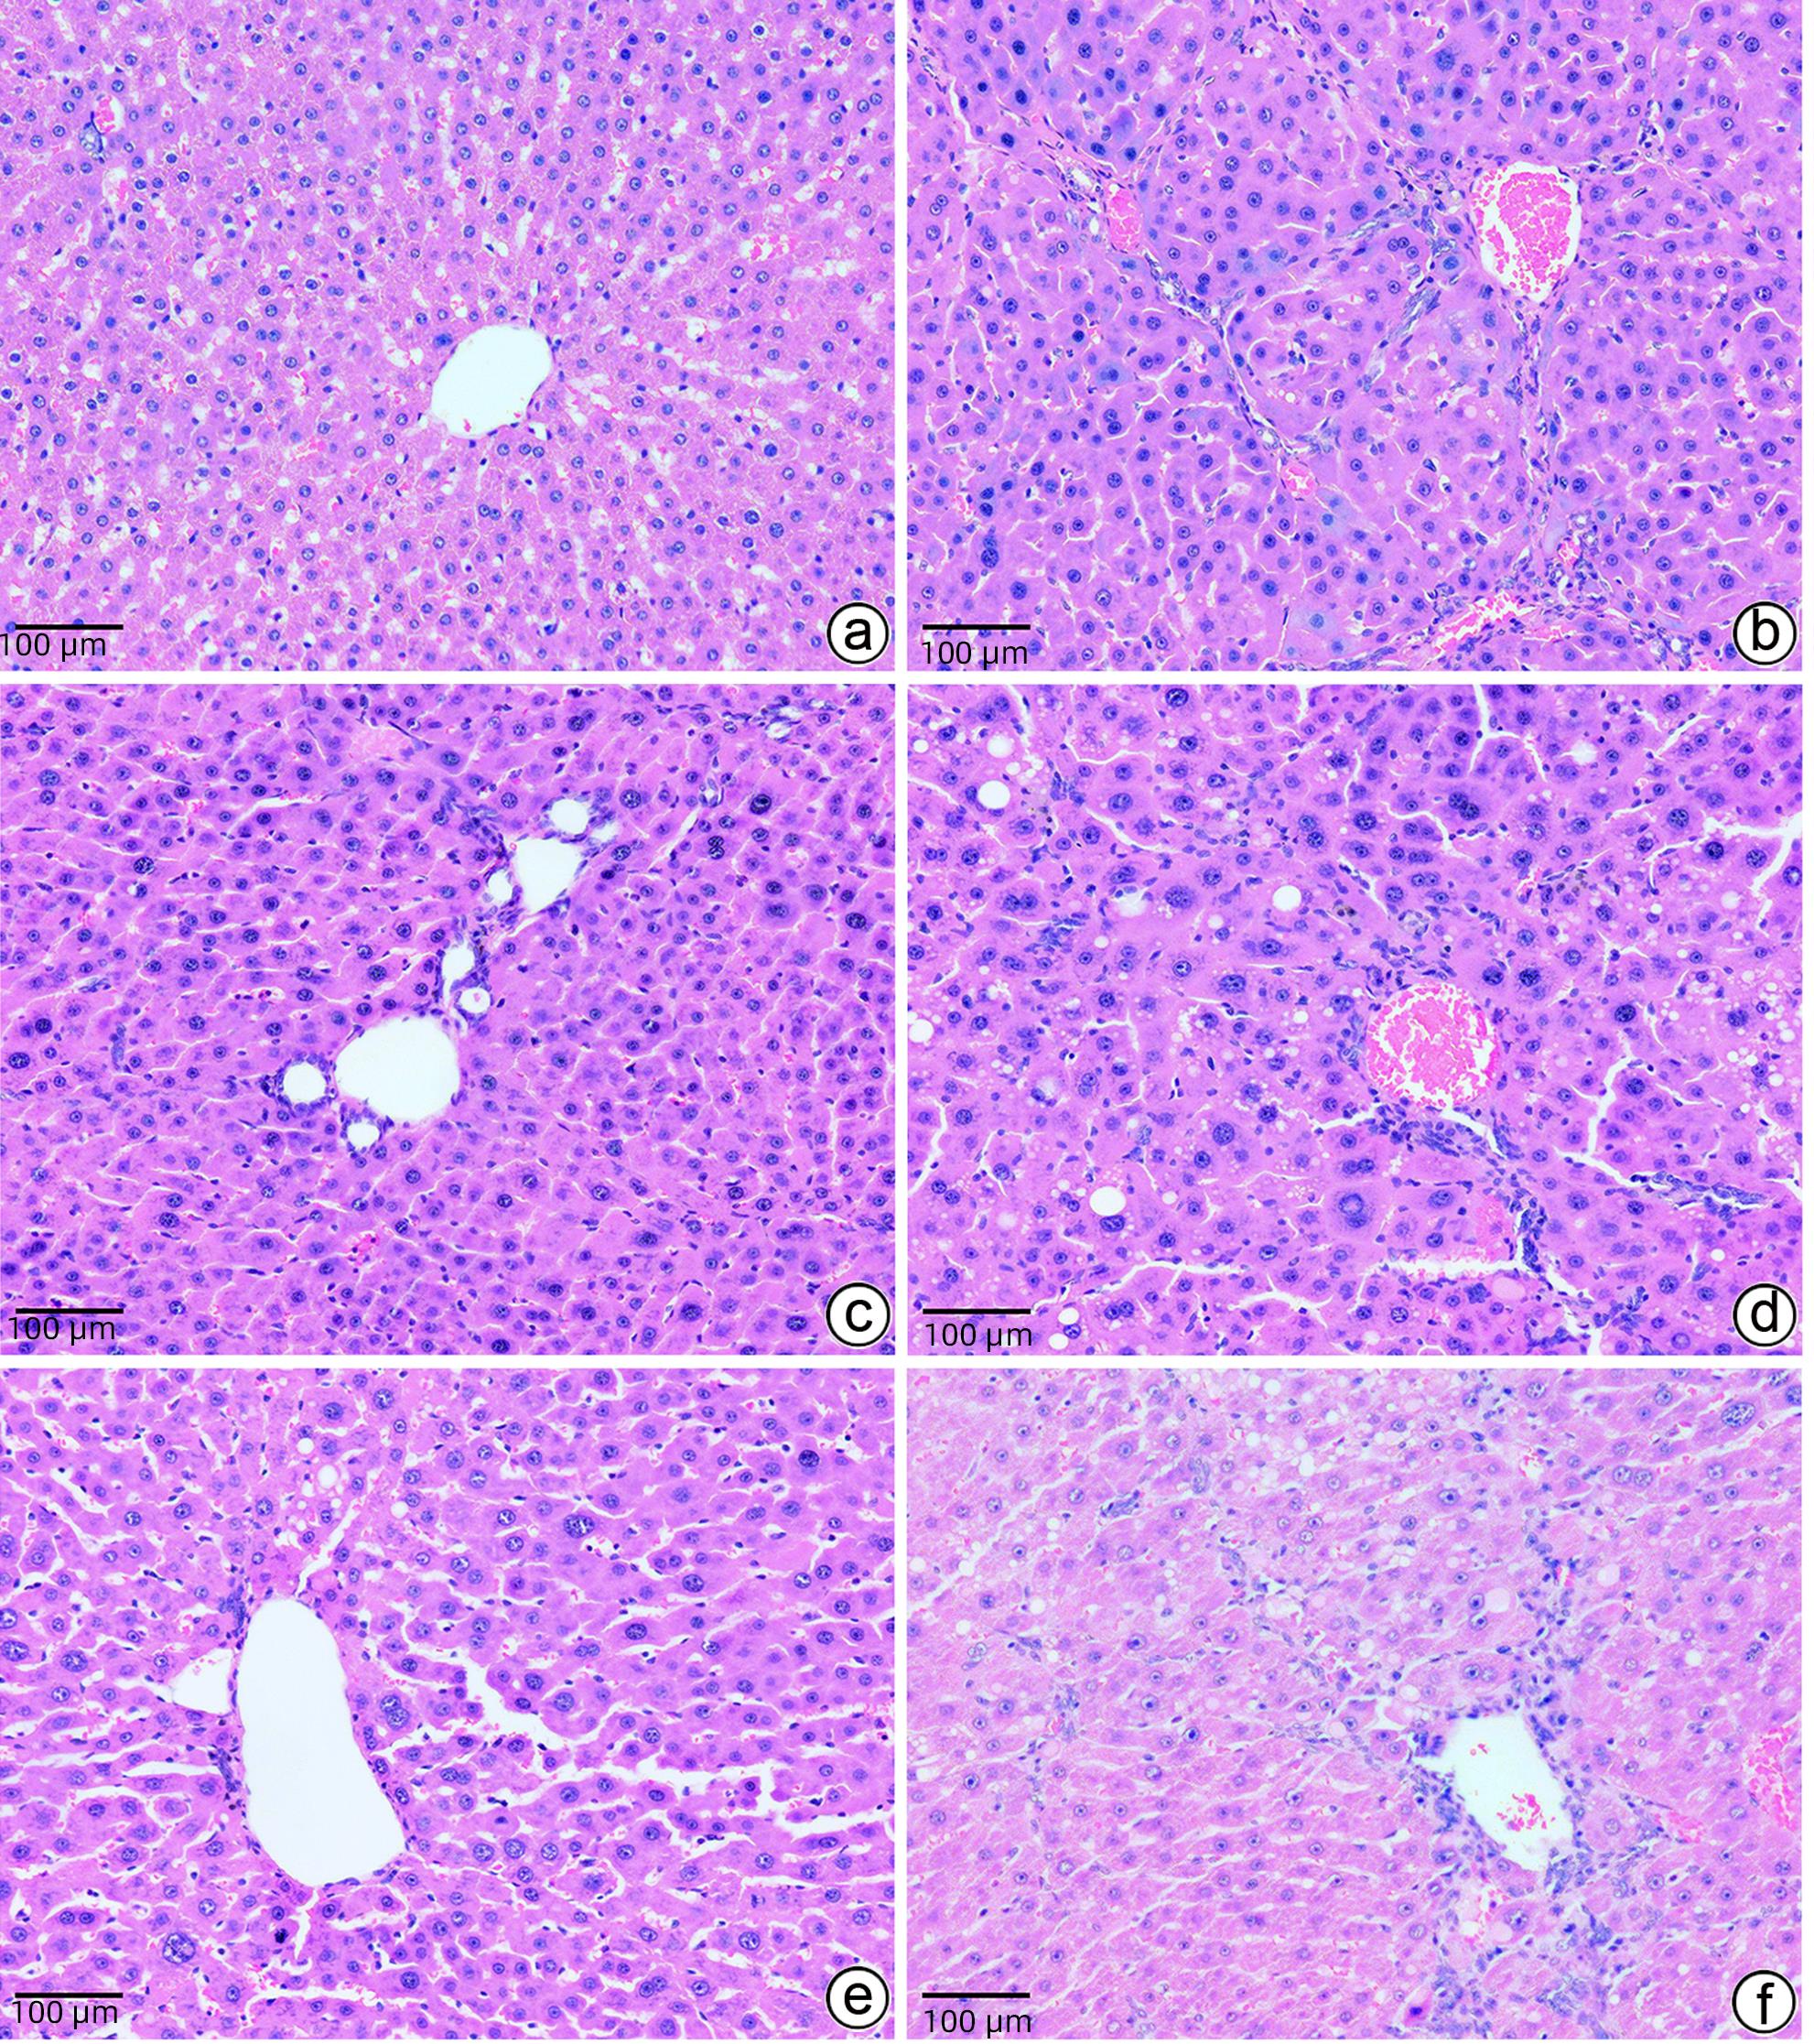

基于PI3K/AKT/mTOR信号通路探讨大黄煎剂对轻微型肝性脑病大鼠脑组织炎症损伤的保护机制

2024, 40(2): 312-318. DOI: 10.12449/JCH240215

摘要(1160) HTML (450) PDF (1982KB)(74)

摘要:

目的  探讨大黄煎剂保留灌肠对轻微型肝性脑病(MHE)大鼠模型脑组织炎症损伤的改善作用及可能机制。  方法  60只SD雄性大鼠按完全随机方法分为空白组(CON组,n=6)和慢性肝硬化造模组(n=54)。12周后慢性肝硬化造模成功并经Morris水迷宫测试确认符合MHE模型大鼠40只,采用完全随机方法分为模型组(MOD组,n=8)、乳果糖组(LT组,n=8)、大黄煎剂低剂量组(RD1组,n=8)、大黄煎剂中剂量组(RD2组,n=8)和大黄煎剂高剂量组(RD3组,n=8)。其中CON组和MOD组大鼠用生理盐水保留灌肠,2 mL/只,1次/d;LT组大鼠用乳果糖按22.5%剂量保留灌肠,2 mL/只,1次/d;RD1组、RD2组、RD3组大鼠分别用大黄煎剂按2.5、5.0、7.5 g/kg三种剂量保留灌肠,2 mL/只,1次/d。所有大鼠治疗10 d后,进行Morris水迷宫测试,分析大鼠的空间学习记忆能力。分析大鼠行为学状态;检测大鼠血清ALT、AST、IL-1β、IL-6、TNF-α和血氨水平;观察大鼠肝组织和脑组织病理学变化;检测大鼠脑组织磷脂酰肌醇3-激酶(PI3K)、蛋白激酶B(AKT)、雷帕霉素靶蛋白(mTOR)的mRNA和蛋白表达水平。计量资料多组间比较采用单因素方差分析,进一步两两比较采用LSD-t检验。  结果  与MOD组比较,RD1组、RD2组和RD3组大鼠逃避潜伏期时间显著缩短(P值均<0.01),ALT、AST、IL-1β、IL-6、TNF-α和血氨水平明显降低(P值均<0.05),肝细胞、脑细胞变性、坏死和炎症程度减轻,脑组织PI3K、AKT、mTOR的mRNA和蛋白表达水平均降低(P值均<0.05),且RD3组治疗效果优于RD1组和RD2组。  结论  大黄煎剂保留灌肠能够改善MHE大鼠认知功能及脑组织炎症损伤,其作用机制可能与调控PI3K/AKT/mTOR信号通路有关。